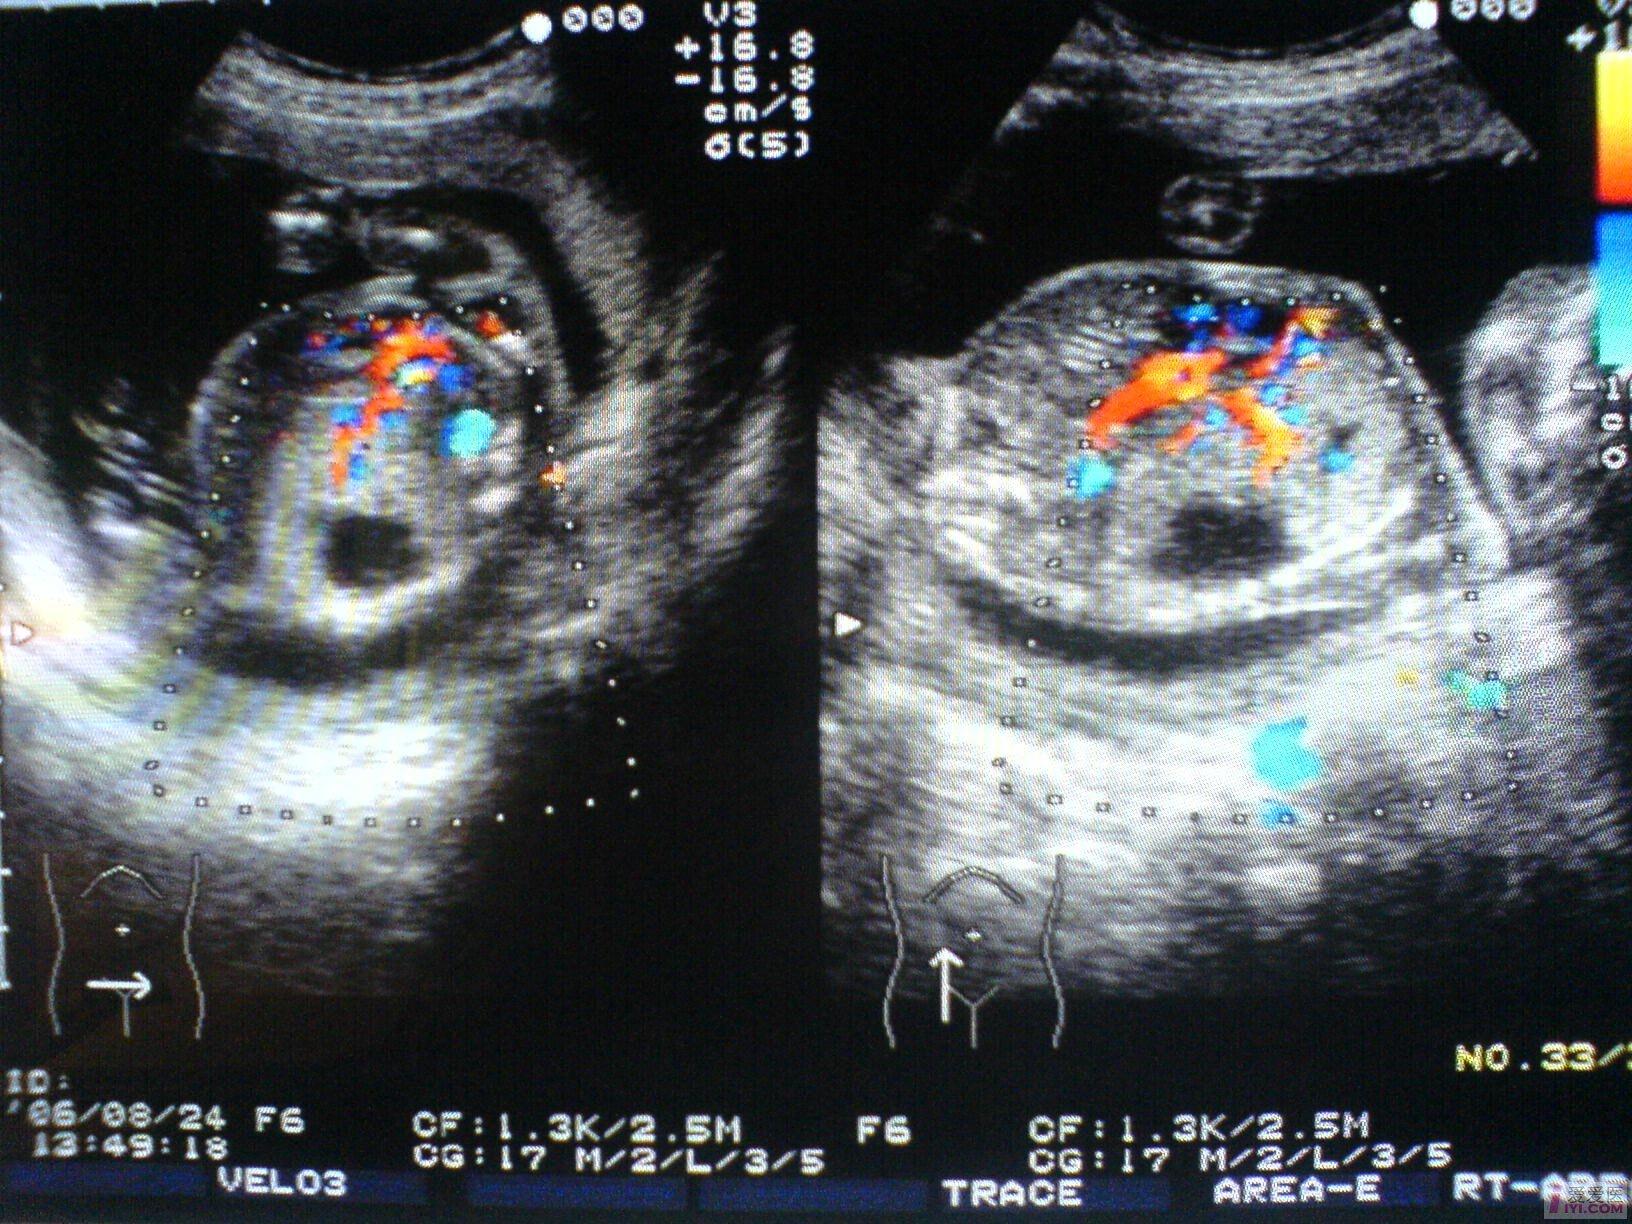

B超所见:宫内单胎妊娠,胎头双顶径51mm,股骨长35mm,胎儿脊柱完整,肺实质回声增强,右侧肺叶内见31X18X17mm不规则无回声区,边界清晰,内透声好,CDFI:无回声区内未见血流信号。胎儿心胸比例失常,心脏明显受压,胎儿肝脏增大,位置下移,占据整个腹腔,回声增粗,欠均匀,未见胃泡回声,肝脏周围见宽4mm无回声暗区。胎动活跃,胎心搏动好,胎心律150bpm,胎盘附于前壁,厚21mm,回声均匀,最大羊水暗区深度74mm,透声好。

B超提示:1.宫内中孕,单胎存活,胎儿发育符合21周。

2.胎儿肺实质回声增强,右侧肺叶囊性占位,肝大,少量腹水。

请教:该例病例可否考虑胎儿肺囊腺瘤样变? [readperm]1[readperm]